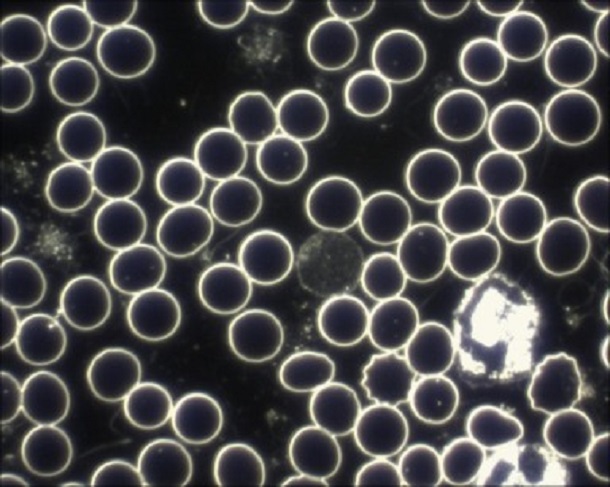

In dieser Aufnahme habe ich für Sie einige Blutbestandteile beschrieben, die Sie im Dunkelfeld sehen können.